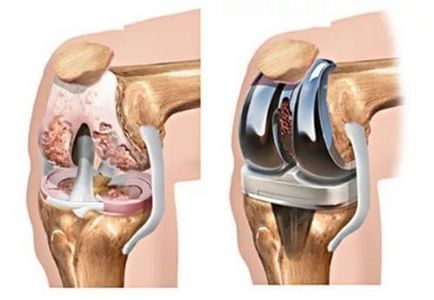

Térdízület cseréje szükséges megsértése esetén a működését és integritását. Az intervenciós eredményez jelentős mozgáskorlátozottságot a közös terület és a súlyos fájdalom. Beszámolók körülbelül térdprotetika más. A legtöbb esetben a betegek elégedettek az intervenciós termelt. Az eredmény a működése függ az orvos tapasztalata és a minősége a protézis. Az alábbiakban az értékelés a betegeket a működés és a rehabilitáció.

Beszámolók körülbelül térdprotetika többnyire pozitív. De nem mindig ez a fajta kezelés is alkalmazható. Az a lehetőség, protézis egyedileg határozzuk meg. Nagy szövődmények kockázata a műtét után már betegeken elhízás 3-4 fokozatú fertőző elváltozások a szervezetben, trombózis, izomsorvadás, a térd. De minden esetben, akkor vegye fel a protézis. Jelenleg 150 típusú implantátumokat. Eredmény protézisek - javítja az életminőséget. De az implantátum hosszú szolgálni csak megfelel minden orvosi ajánlásokat.